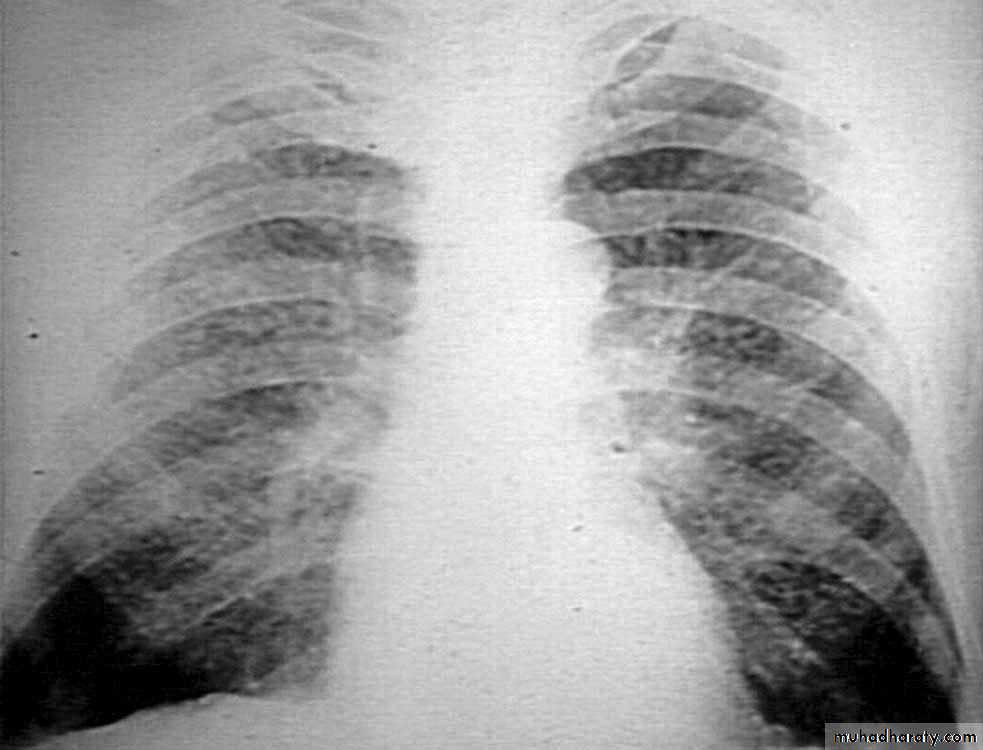

Chest X-ray: typically small lung volumes with reticulonodular shadowing

Abnormal chest X-ray at presentation with lower zone bi-basal reticular and reticulonodular opacities. 'honeycomb' appearance in advanced disease.